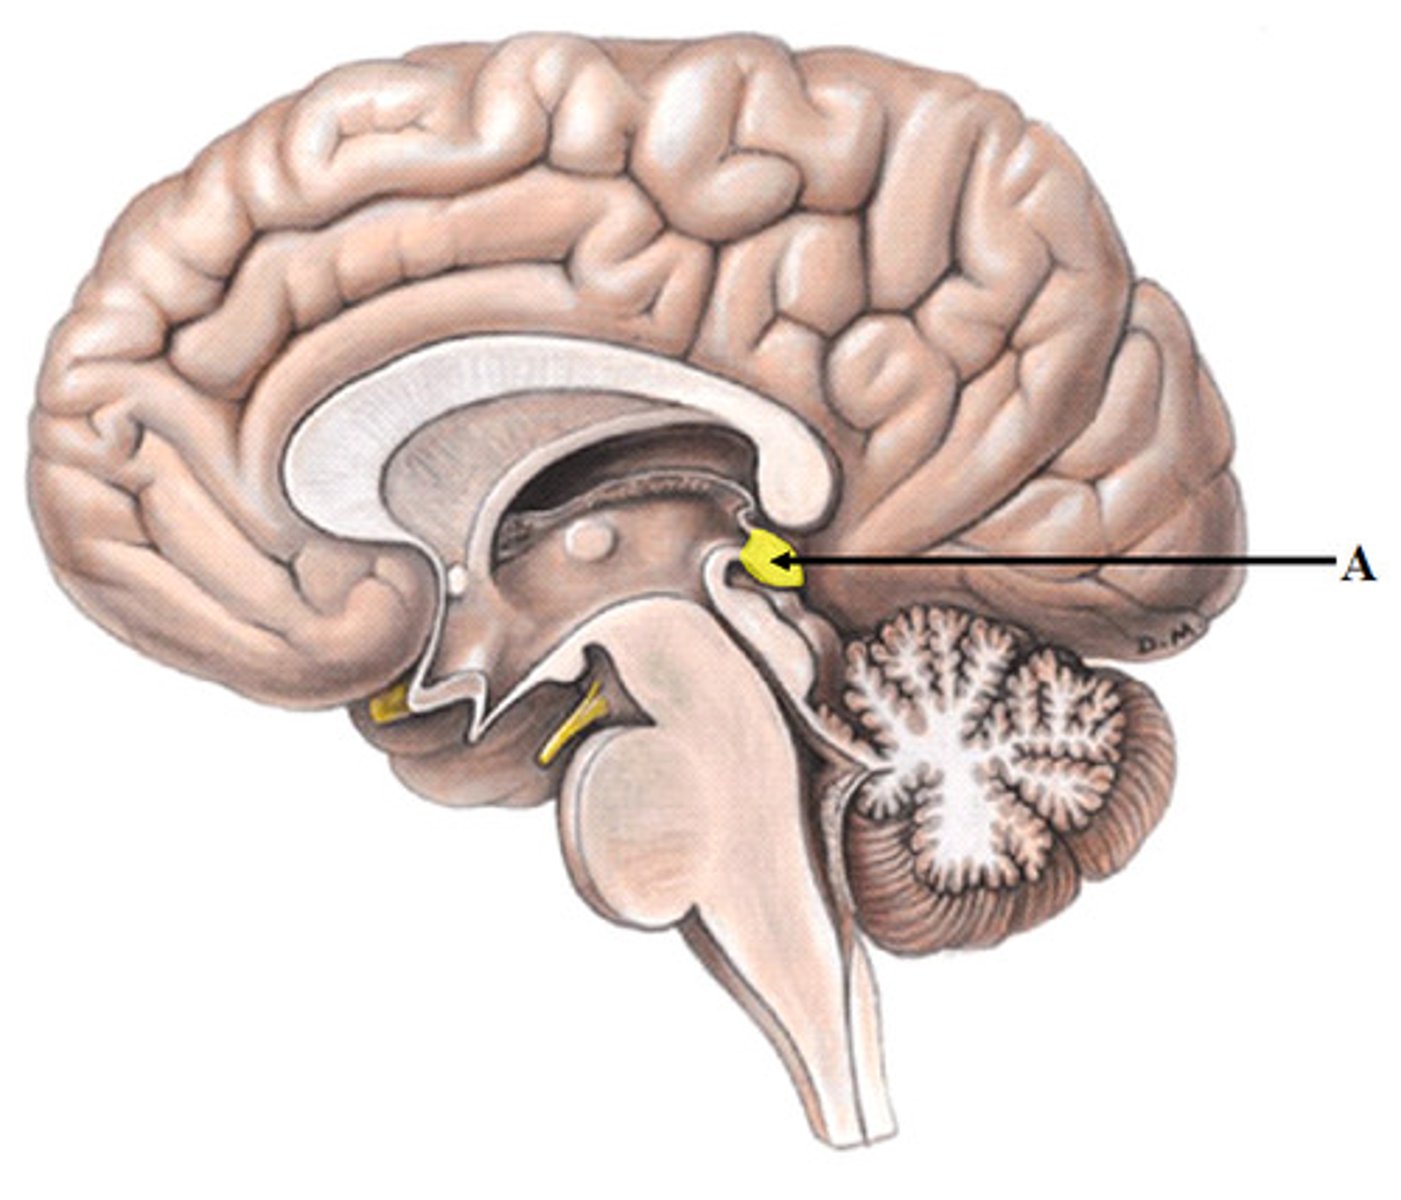

hypophysis (pituitary gland)

infundibulum

pineal gland